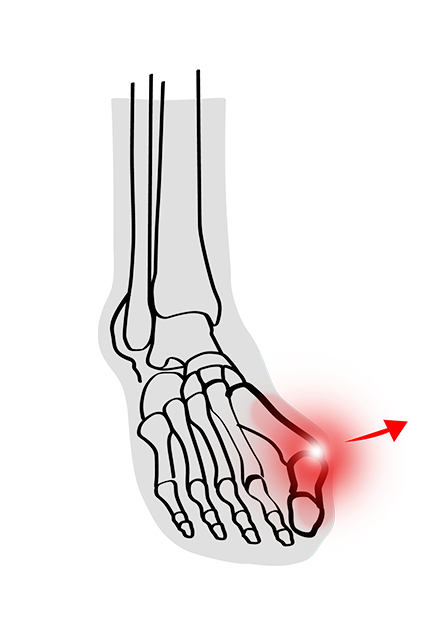

Hast du dich schon einmal gefragt, was diese knöcherne Erhebung an der Seite deines Fusses ist? Möglicherweise handelt es sich um einen Ballenzeh, auch als Hallux valgus bekannt. Obwohl ein Hallux valgus in den meisten Fällen relativ harmlos ist und oft keinen medizinischen Eingriff erfordert, kann er unbehandelt jedoch eine Menge Schmerzen und Beschwerden verursachen und deine Lebensqualität drastisch einschränken.